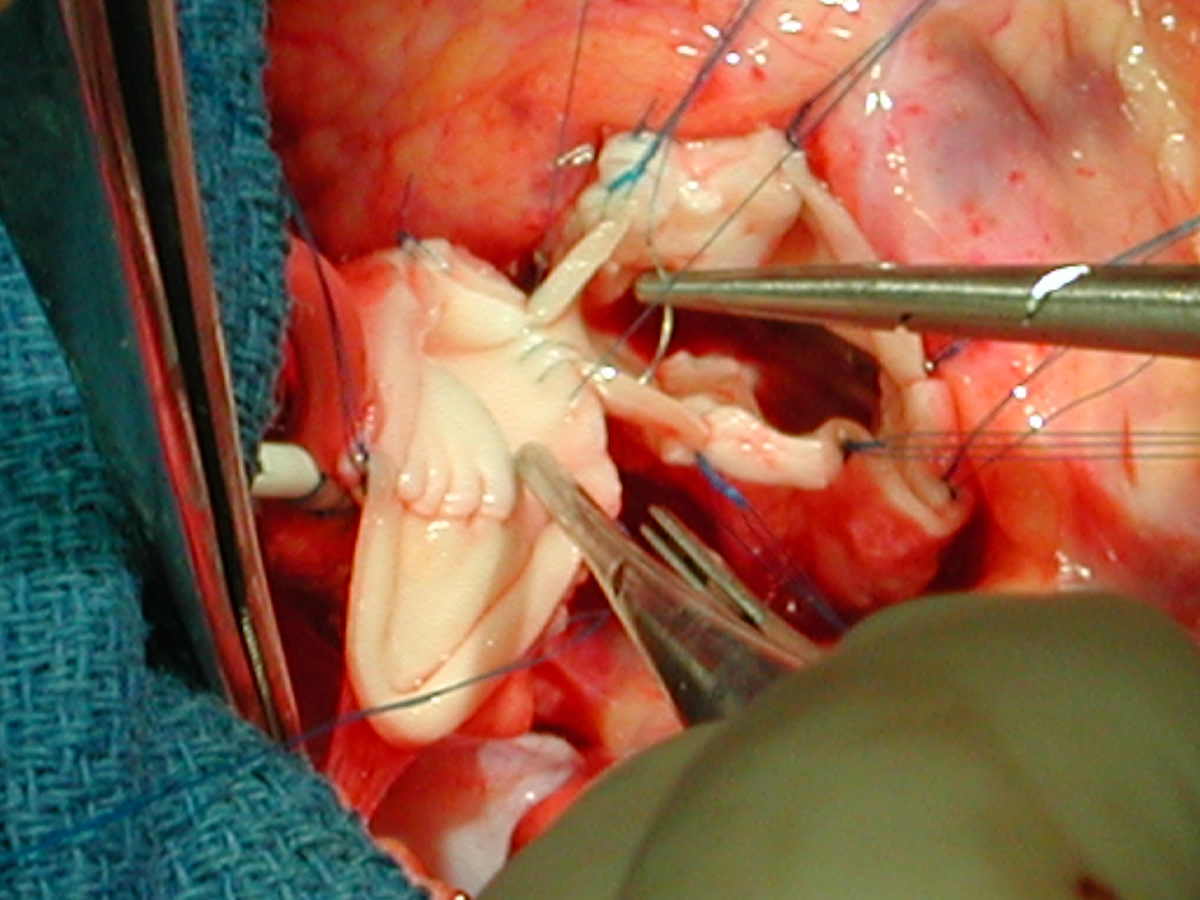

Figures 20 & 21: Third incision has been made to the right of the left coronary orifice. They yellow plastic suture boot on the pickup is pointing out the left coronary orifice. Figures 22 & 23: Proximal ascending aorta now opens widely, revealing the right and left coronary orifices and the normal trileaflet aortic valve below.

Figure Figure Figure Figure